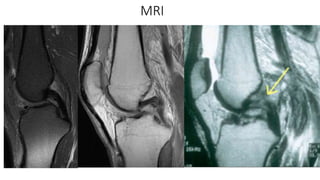

MRI

Sensitivity 97%

Specificity 100%

Empty Notch Sign

Bone Bruising